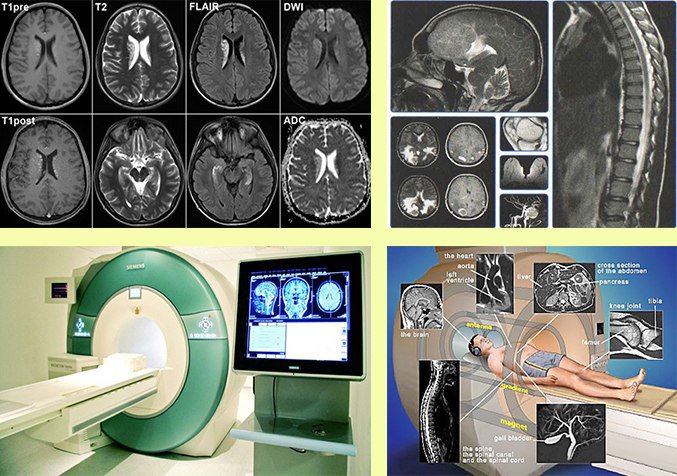

Для чтения сканограмм, полученных в результате процедуры мрт, нужно не только профильное образование, но и немалый опыт практической работы. Преимущество метода в том, что он не только визуализирует имеющуюся картину, но и помогает установить причину недуга. Как уже говорилось выше, в таких случаях мы разбиваем исследование на части. Современные аппараты мрт дают очень точные результаты.

После томографии на полученных снимках видны ткани, отображенные просветлениями, а также затемнениями.

Метод безопасный, показательный и неинвазивный. Мрт показывает функциональные и анатомические нарушения строения головного мозга.